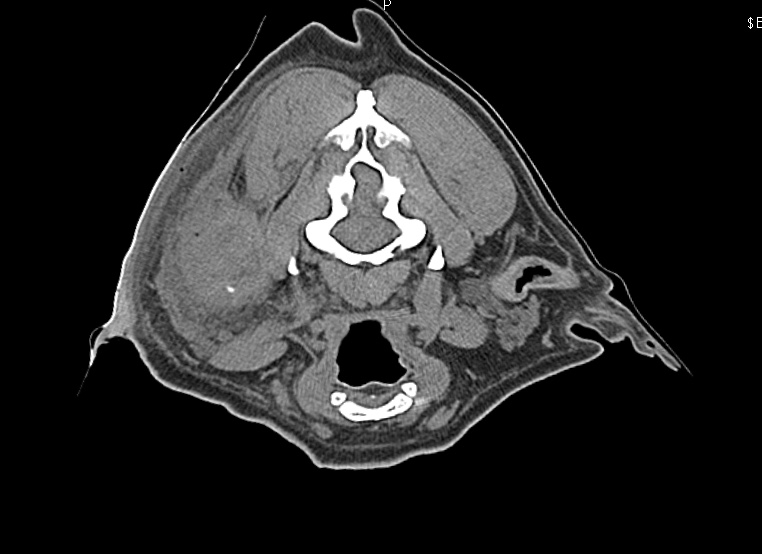

CT検査により外耳から中耳に至る腫瘤の存在が疑われ、耳道軟骨は骨化し、化膿巣は目の下から首にまで達していました。

耳道レベルの腫れ、白いのは骨化し崩れた外耳道